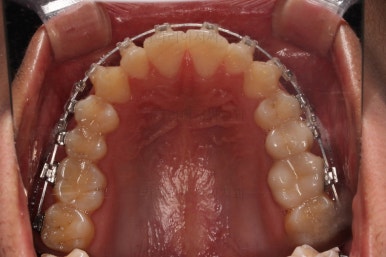

초진 시 입안의 모습입니다.

앞니가 약간 삐뚠 것 말고는 큰 문제는 없어보이네요.

장치를 부착했습니다.

이번 부산연제구교정 환자분이 선택한 장치는 엠파워 클리어라고 하는 자가결찰 세라믹 장치입니다.